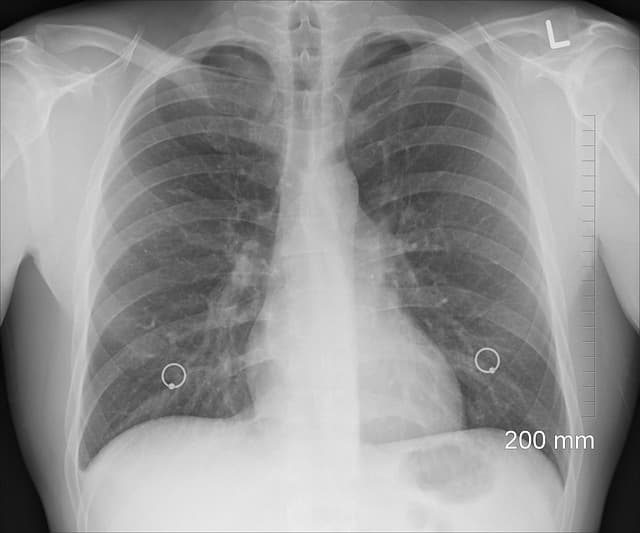

**급성호흡곤란증후군(Acute Respiratory Distress Syndrome, ARDS)**는 성인과 소아 모두에서 치명적인 상태를 초래할 수 있는 폐 질환입니다. ARDS는 폐포의 염증과 손상으로 인해 산소화가 저하되고 환기 장애가 발생하는 질환으로, 성인과 소아에서 그 발병 기전, 임상 양상, 치료 접근법이 다르게 나타납니다. 본 글에서는 성인 ARDS와 소아 ARDS의 차이를 살펴보고, 특히 소아 ARDS에서 효과적으로 사용되는 **고빈도진동환기(High Frequency Oscillation Ventilation, HFOV)**에 대해 논의하겠습니다.

• 임상 양상: 급격한 저산소혈증, 양측 폐침윤이 특징이며, 폐의 순응도가 심각하게 저하됩니다.

• 임상 양상: 저산소혈증과 폐침윤은 성인과 유사하지만, 폐의 순응도 저하가 덜 뚜렷할 수 있습니다. 이는 소아의 폐가 더 "유연성"을 가지기 때문입니다.